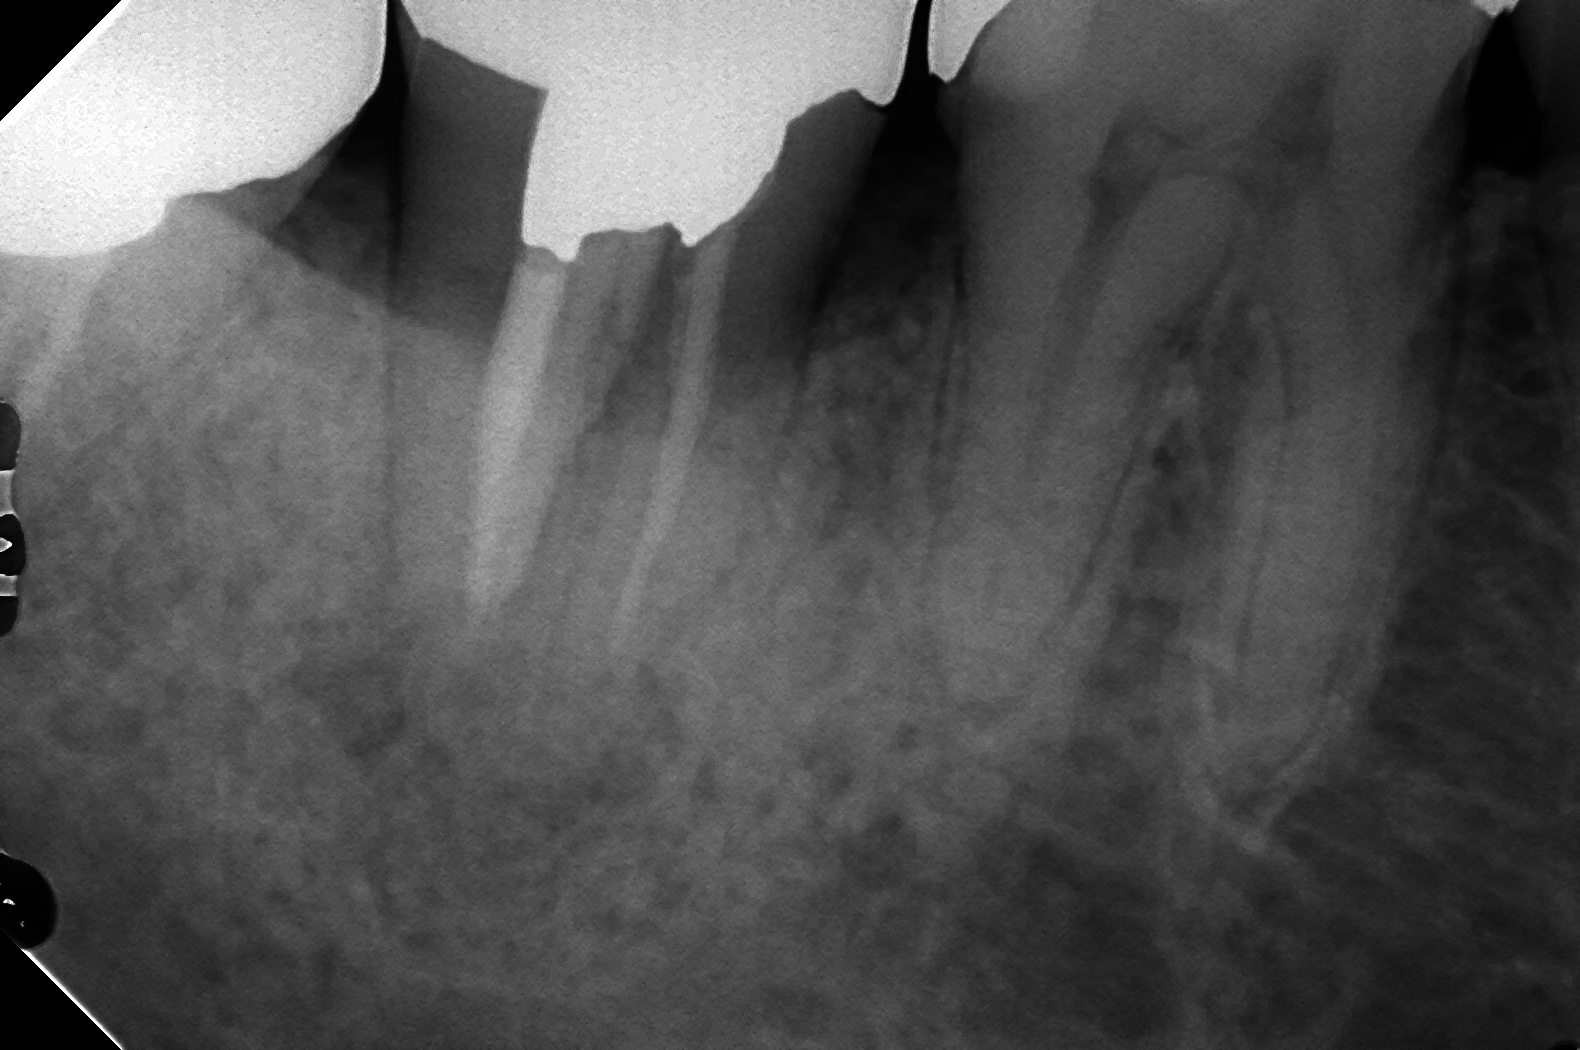

C2です。

術後3カ月のレントゲンです。

綺麗に治りましたね(^^♪